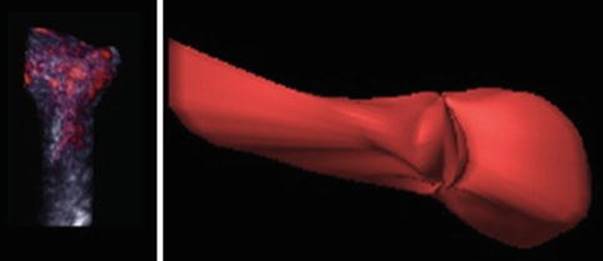

Fig. 2.2

Ovarian volume

The optimum cut-off value for hyper-response of AFC is ≥14 with a sensitivity of 82 % and specificity 89 % to predict ovarian hyperstimulation syndrome (OHSS). The ovarian volume also correlates with the number of growing follicles, but not with the number of oocytes retrieved [2]. It was also observed that women with small ovaries with a volume of less than 3 cm3 have a very high cancellation rate of in vitro fertilization (IVF) [3]. 3-dimensional ultrasound allows more precise calculation of ovarian and stromal volumes (Fig. 2.2). However, yet again, the predictive value for pregnancy by measuring the ovarian and stromal volume is limited (1.0–1.4) [4, 5].